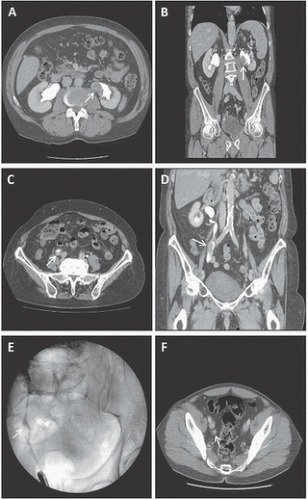

Although there are some differences in patient positioning and surgical technique by approach selected, patient preparation is similar for all patients undergoing minimally invasive nephroureterectomy. Staging is performed for all patients as described earlier including cross-sectional imaging combined with upper tract opacification (Fig. 7.1). This allows for the accurate anatomic evaluation of any upper tract disease, definition of the renal hilar vascular anatomy as well as the presence of lymphadenopathy or solid organ metastases. In addition, patients undergo preoperative lab evaluation with a comprehensive metabolic panel including liver function tests, complete blood count, coagulation panel, electrocardiogram, and blood type and screen. We do not cross-match for blood products given the low incidence of blood transfusion associated with this procedure. In addition, patients undergo preoperative evaluation by anesthesiology with directed evaluation by cardiology, pulmonology, or other medical services as indicated. Mechanical bowel preparation is not necessary; a clear liquid diet beginning 24 hours prior to surgery with nothing by mouth 4 hours prior to surgery is recommended.